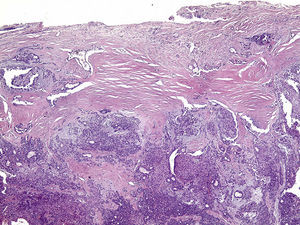

Os cortes histológicos, corados em hematoxilina e eosina, mostraram neoplasia de glândula salivar benigna, constituída por células epiteliais e mioepiteliais, parcialmente envolvida por fina cápsula de tecido conjuntivo fibroso (fig. 5). As células epiteliais encontravam‐se formando lençóis ou estruturas ductiformes, enquanto as células mioepiteliais formavam áreas mixoides, hialinas (fig. 6) ou exibiam aspecto plasmocitoide (fig. 7). O diagnóstico de adenoma pleomórfico foi confirmado. Paciente queixou‐se de desconforto no palato quando se alimentava, durante as 2 primeiras semanas após cirurgia. O paciente está sendo acompanhado clinicamente e, 2 anos após a cirurgia, não apresenta sinais de recidiva da lesão (fig. 8).

Os cortes histológicos mostraram neoplasia benigna de glândula salivar, envolvida por cápsula de tecido conjuntivo fibroso (fig. 14). O parênquima neoplásico é constituído por células epiteliais dispostas em lençóis e estruturas ductiformes, além de células mioepiteliais formando áreas mixoides e hialinas (fig. 15) ou apresentando‐se com morfologia plasmocitoide (fig. 16). O diagnóstico de adenoma pleomórfico foi confirmado. A paciente relatou ausência de dor no pós‐operatório e manteve utilização da placa de acrílico por 4 semanas. A paciente encontra‐se em acompanhamento e o exame clínico após 2 anos da remoção cirúrgica mostrou adequada cicatrização e ausência de sinais de recidiva da lesão (fig. 17).